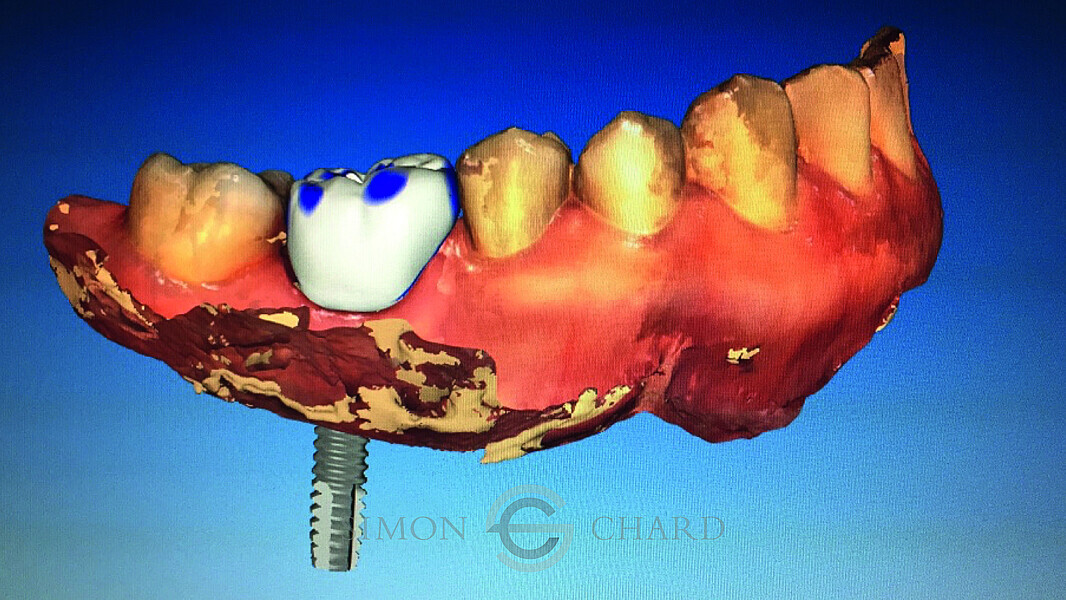

Implant restoration with CEREC